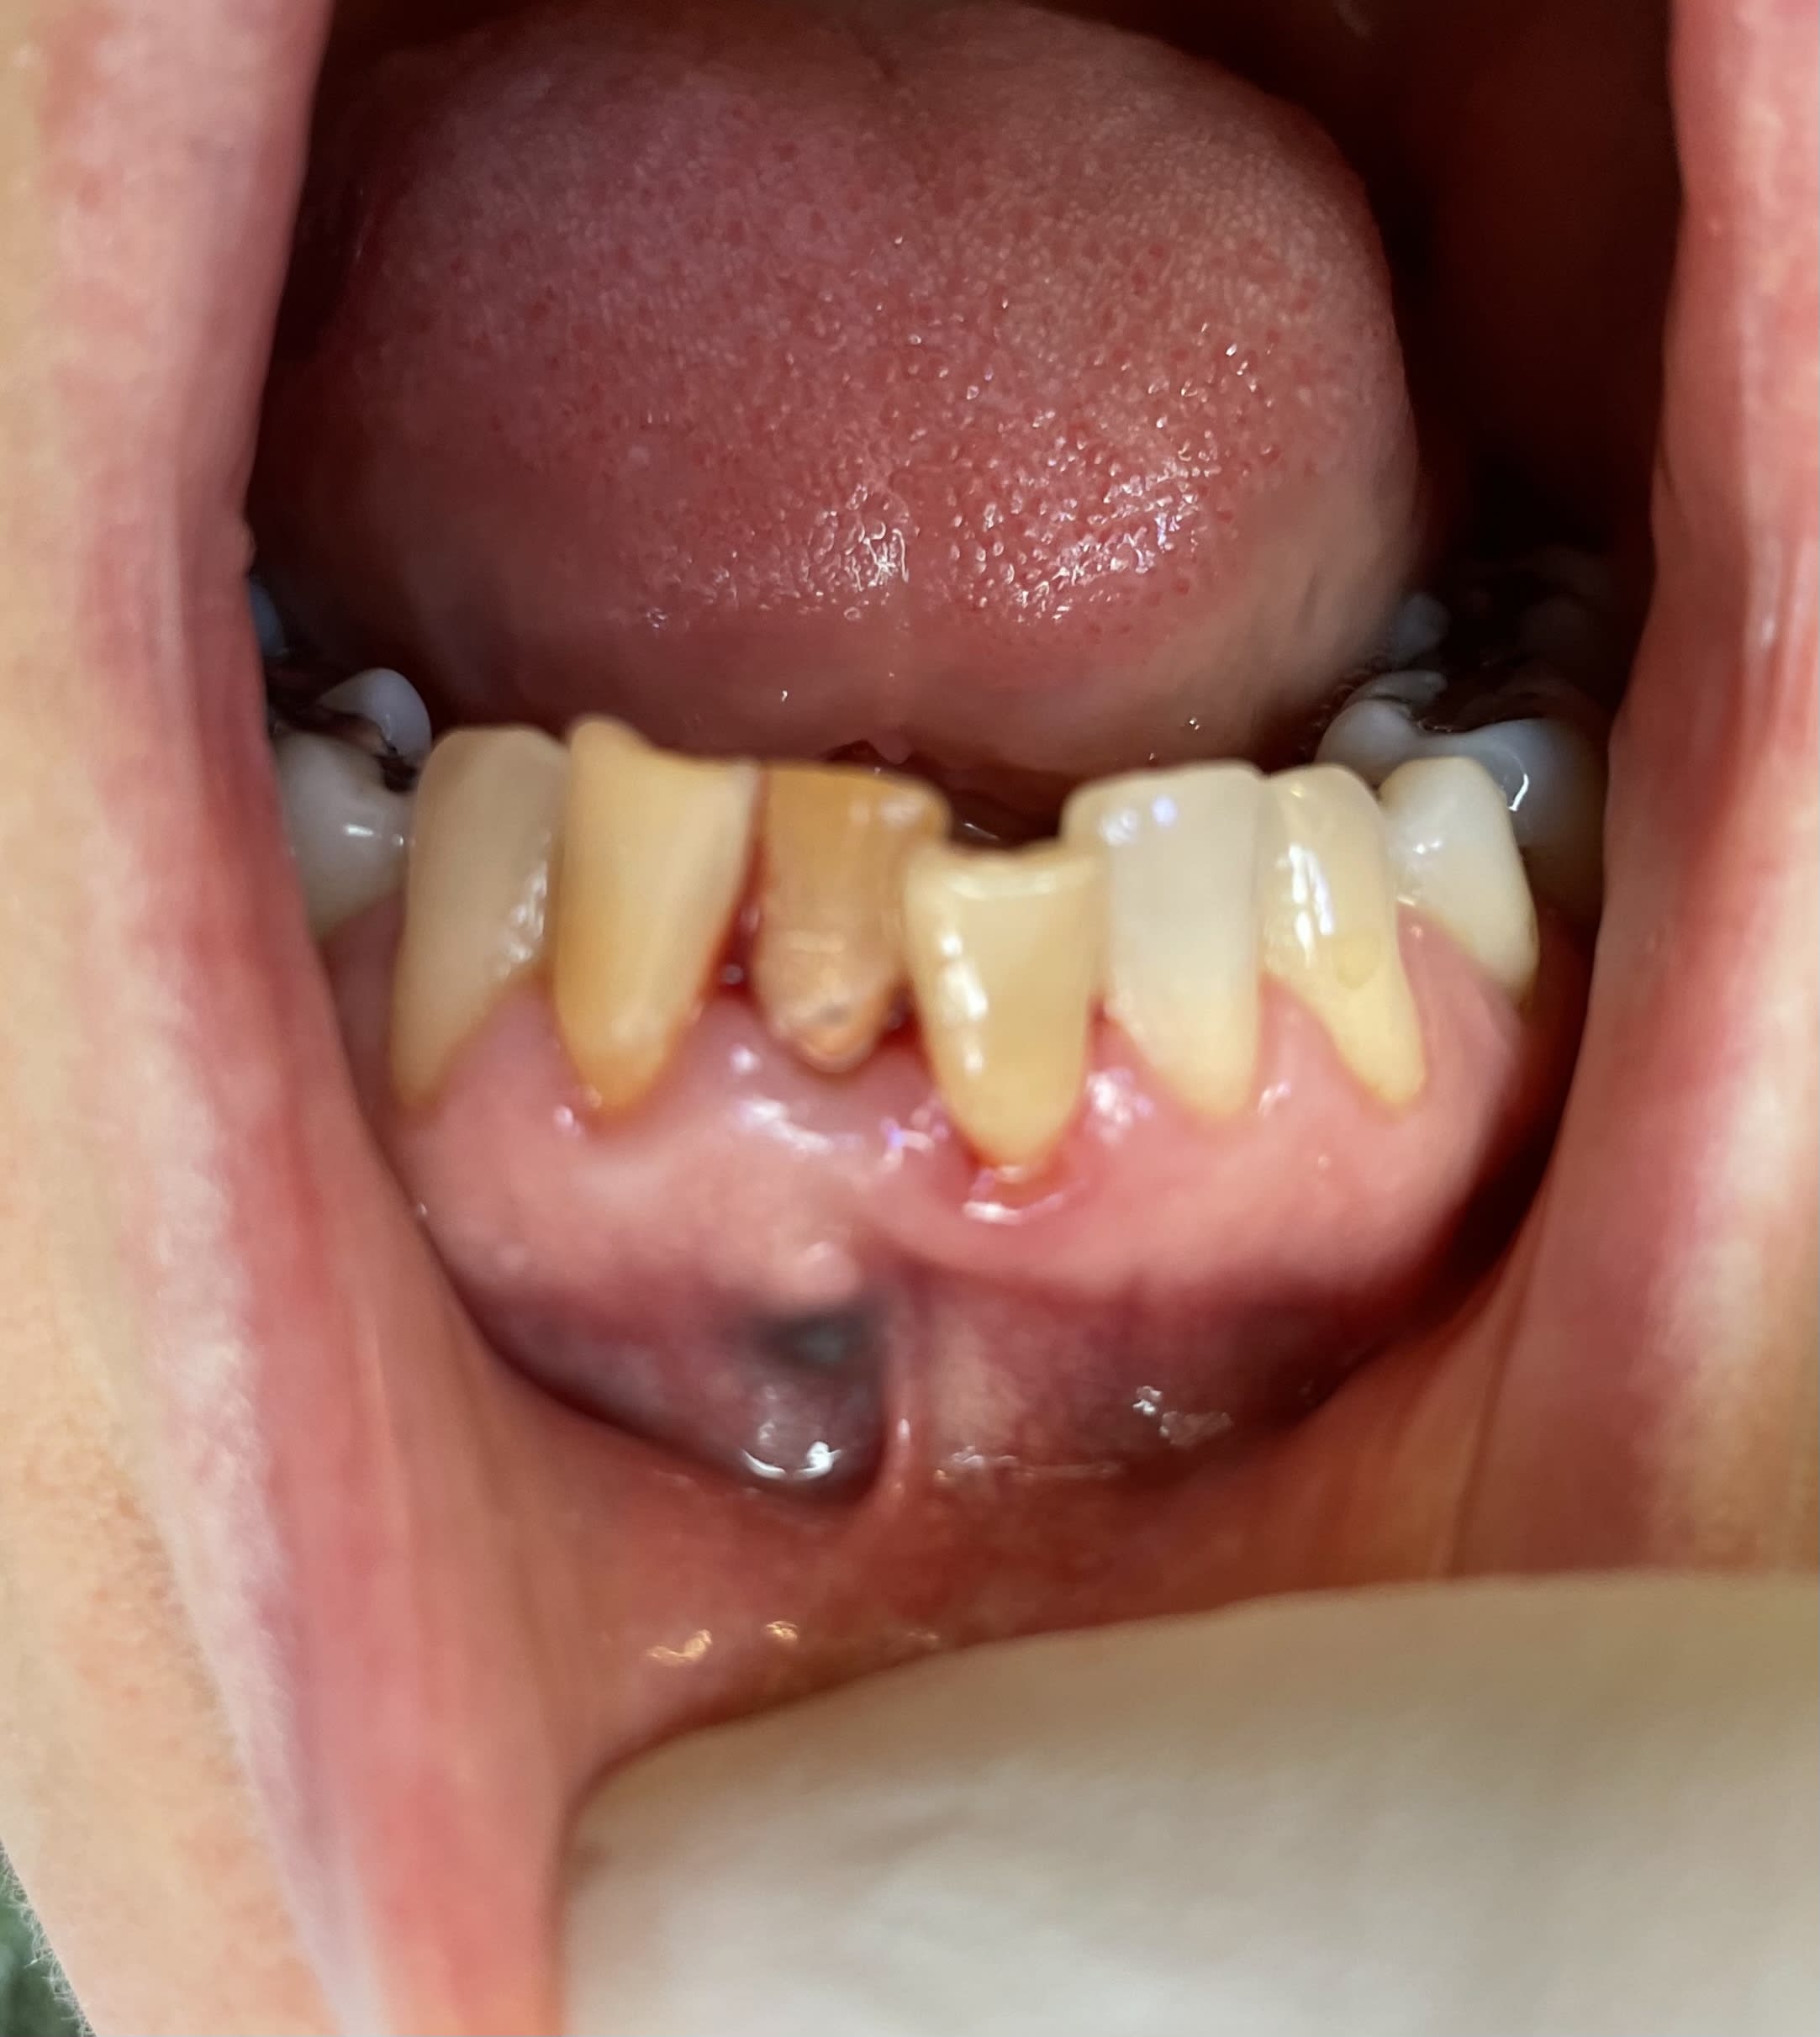

alors , elle perd , elle casse toutes les dents les unes après les autres sauf la 25 .

peuchere , d elle , chaque fois qu elle va voir un dentiste , on la prend pour une jobarde , et on la prend à coup de pieds . et tu sais pourquoi ? pcq elle leurs dit qu' il ne faut pas y toucher à la 25 que c est une dent qu on lui a enlevé puis remise , c est un souvenir ! puis tu peux y aller elle bronche pas la 25 .

mais toi tu la connais l histoire , mais ouiiiii , ç est celle de la page 3 ( 2014)